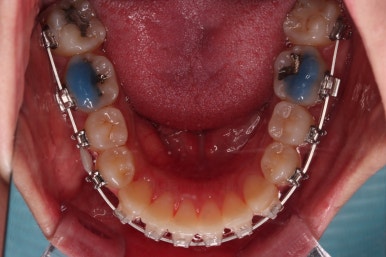

초진 시 입안의 모습입니다.

전반적으로 치열이 삐뚤고요.

위아래 중앙선이 약간 틀어져 있는데 많이 심한 편은 아니고요. 윗니가 배열된 U자 형태를 보면 아랫니보다 좁은 형태로 "악궁이 좁은" 상황이었습니다.

3. 치료경과

악궁확장을 먼저 시행합니다.

아랫니에 비해서 윗니의 악궁의 폭이 좁기 때문에 가로폭을 먼저 개선합니다.

악궁확장 이후, 유지단계 동안 확장의 유지에 필요한 치아를 제외하고는 브라켓을 부착하게 됩니다.